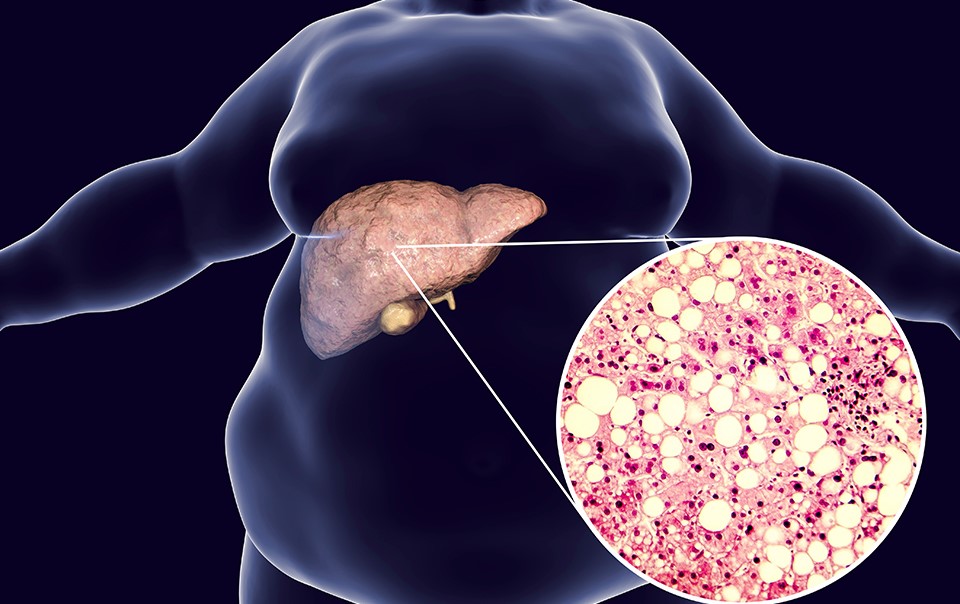

Kathmandu — Fatty liver disease is a condition in which excess fat accumulates in the liver, an essential organ that helps digest food, process nutrients, and remove toxins from the body. When the liver becomes fatty and weakened, it can disrupt numerous bodily functions.

According to MedlinePlus, fatty liver disease occurs when excess fat builds up in the liver. It can be categorized into two types:

NAFLD is more commonly found in individuals with type 2 diabetes, obesity, or prediabetic conditions. The exact cause is still not fully understood, but poor diet and sedentary lifestyles are key contributors.